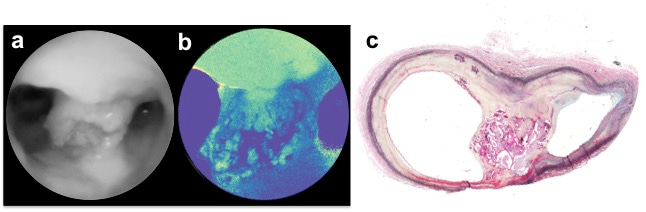

Once we had a good understanding of the different angioscopic patterns of normal and abnormal endoluminal anatomy, and were able to differentiate complicated from non-complicated atherosclerotic plaques with a high grade of certainty, we decided to explore the possibility of employing differences in tissue autofluorescence as a means of dissecting the biochemical makeup of plaques. To this end, we analyzed the fluorescent spectra of the major structural constituents of normal arteries and atherosclerotic plaques with lasers in the blue and green wavelength, and corroborated the finding with confocal microscopy of unstained tissue sections. We then used this information to co-generate label-free biochemical contrast derived from arterial autofluorescence with structural images of the SFE (Figure 2), and derived a multimodal classifier capable of categorizing the full spectrum of atherosclerotic lesions according to the histopathological classification of the American Heart Association (AHA).

Figure 2 | Scanning

fiber angioscopic images with red reflectance for structural images (a), blue

fluorescence for label-free biochemical contrast (b), and multimodal overlapped

image (c). Histology showed an intermediate atherosclerotic plaque rich in macrophages

(d), with very low fluorescence in the blue spectrum in comparison to the

elastin in the tunica media, as shown in confocal microscopy (e).